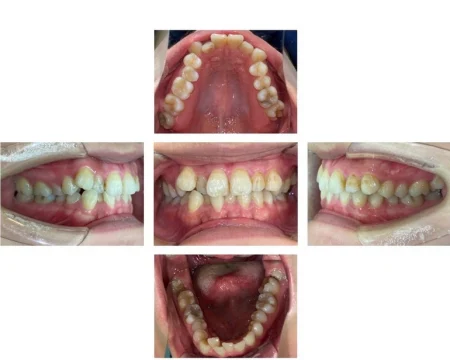

20代女性「オンライン授業中に映る自分の口元が気になる」歯が重なり合ってデコボコしている歯並びをマウスピース型矯正「インビサラインフル」により歯を抜かずきれいに整えた症例

拝見したところ、上下の前歯ともに、歯が重なり合ってデコボコした状態の「叢生(そうせい)」でした。

前歯以外、奥歯にかけて(臼歯部/4番以降)は正常な歯並びでした。

遠方からご来院される患者様でしたので、

という理由から、マウスピース型矯正「インビザラインフル」をご提案しました。

また、遠方の患者様に対して抜歯をともなう矯正治療を行った場合、トラブルがあったときにすぐにご来院いただけなかったり、治療回数も増えたりする可能性があるため、歯を抜かない矯正治療で進めました。